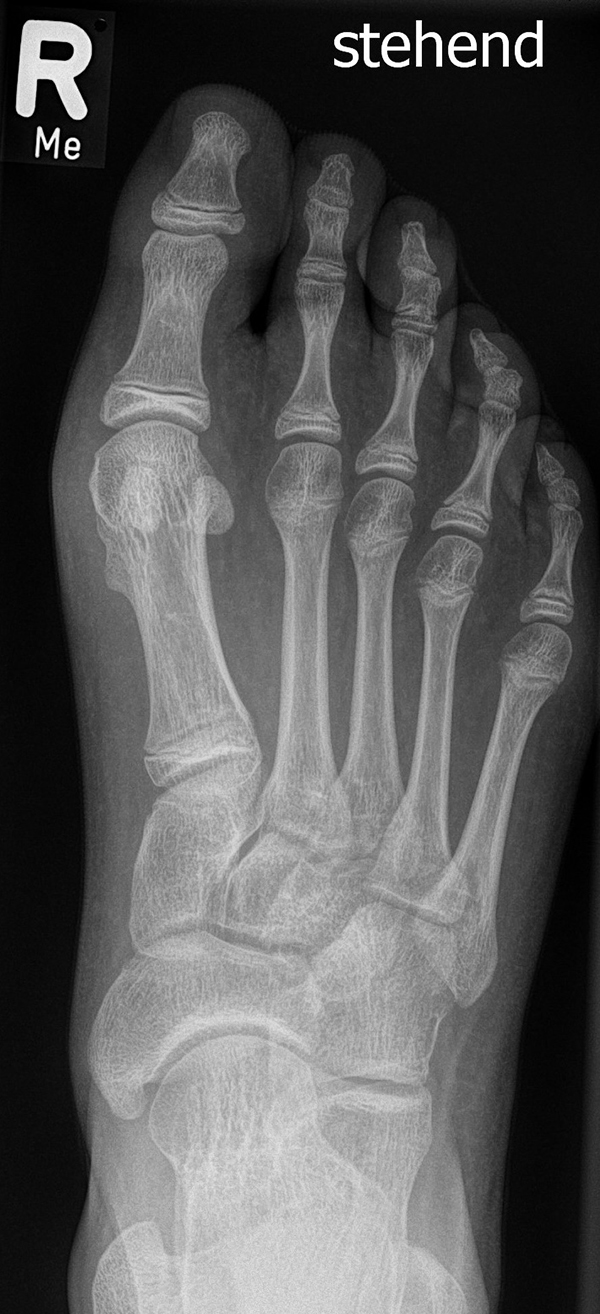

Abb. 2 a-c: offene Wachstumsfugen MT I Basis und Zehen (a), teilweise geöffnete Wachstumsfugen (b) und geschlossene Wachstumsfugen (c).